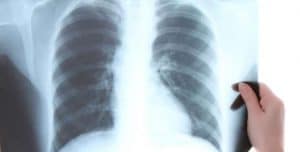

El azote de la tuberculosis – Proyecto científico EuropeoContenidos Arranca ERA4TB (European régimen Accelerator for Tuberculosis). Consorcio científico internacional para acelerar el desarrollo de tratamientos integrales contra la tuberculosis L&S.- ERA4TB (European régimen Accelerator for Tuberculosis) es el nombre de un proyecto europeo parte de uno mayor de orden mundial para conseguir nuevos tratamientos contra … Sigue leyendo ERA4TB – European régimen Accelerator for Tuberculosis